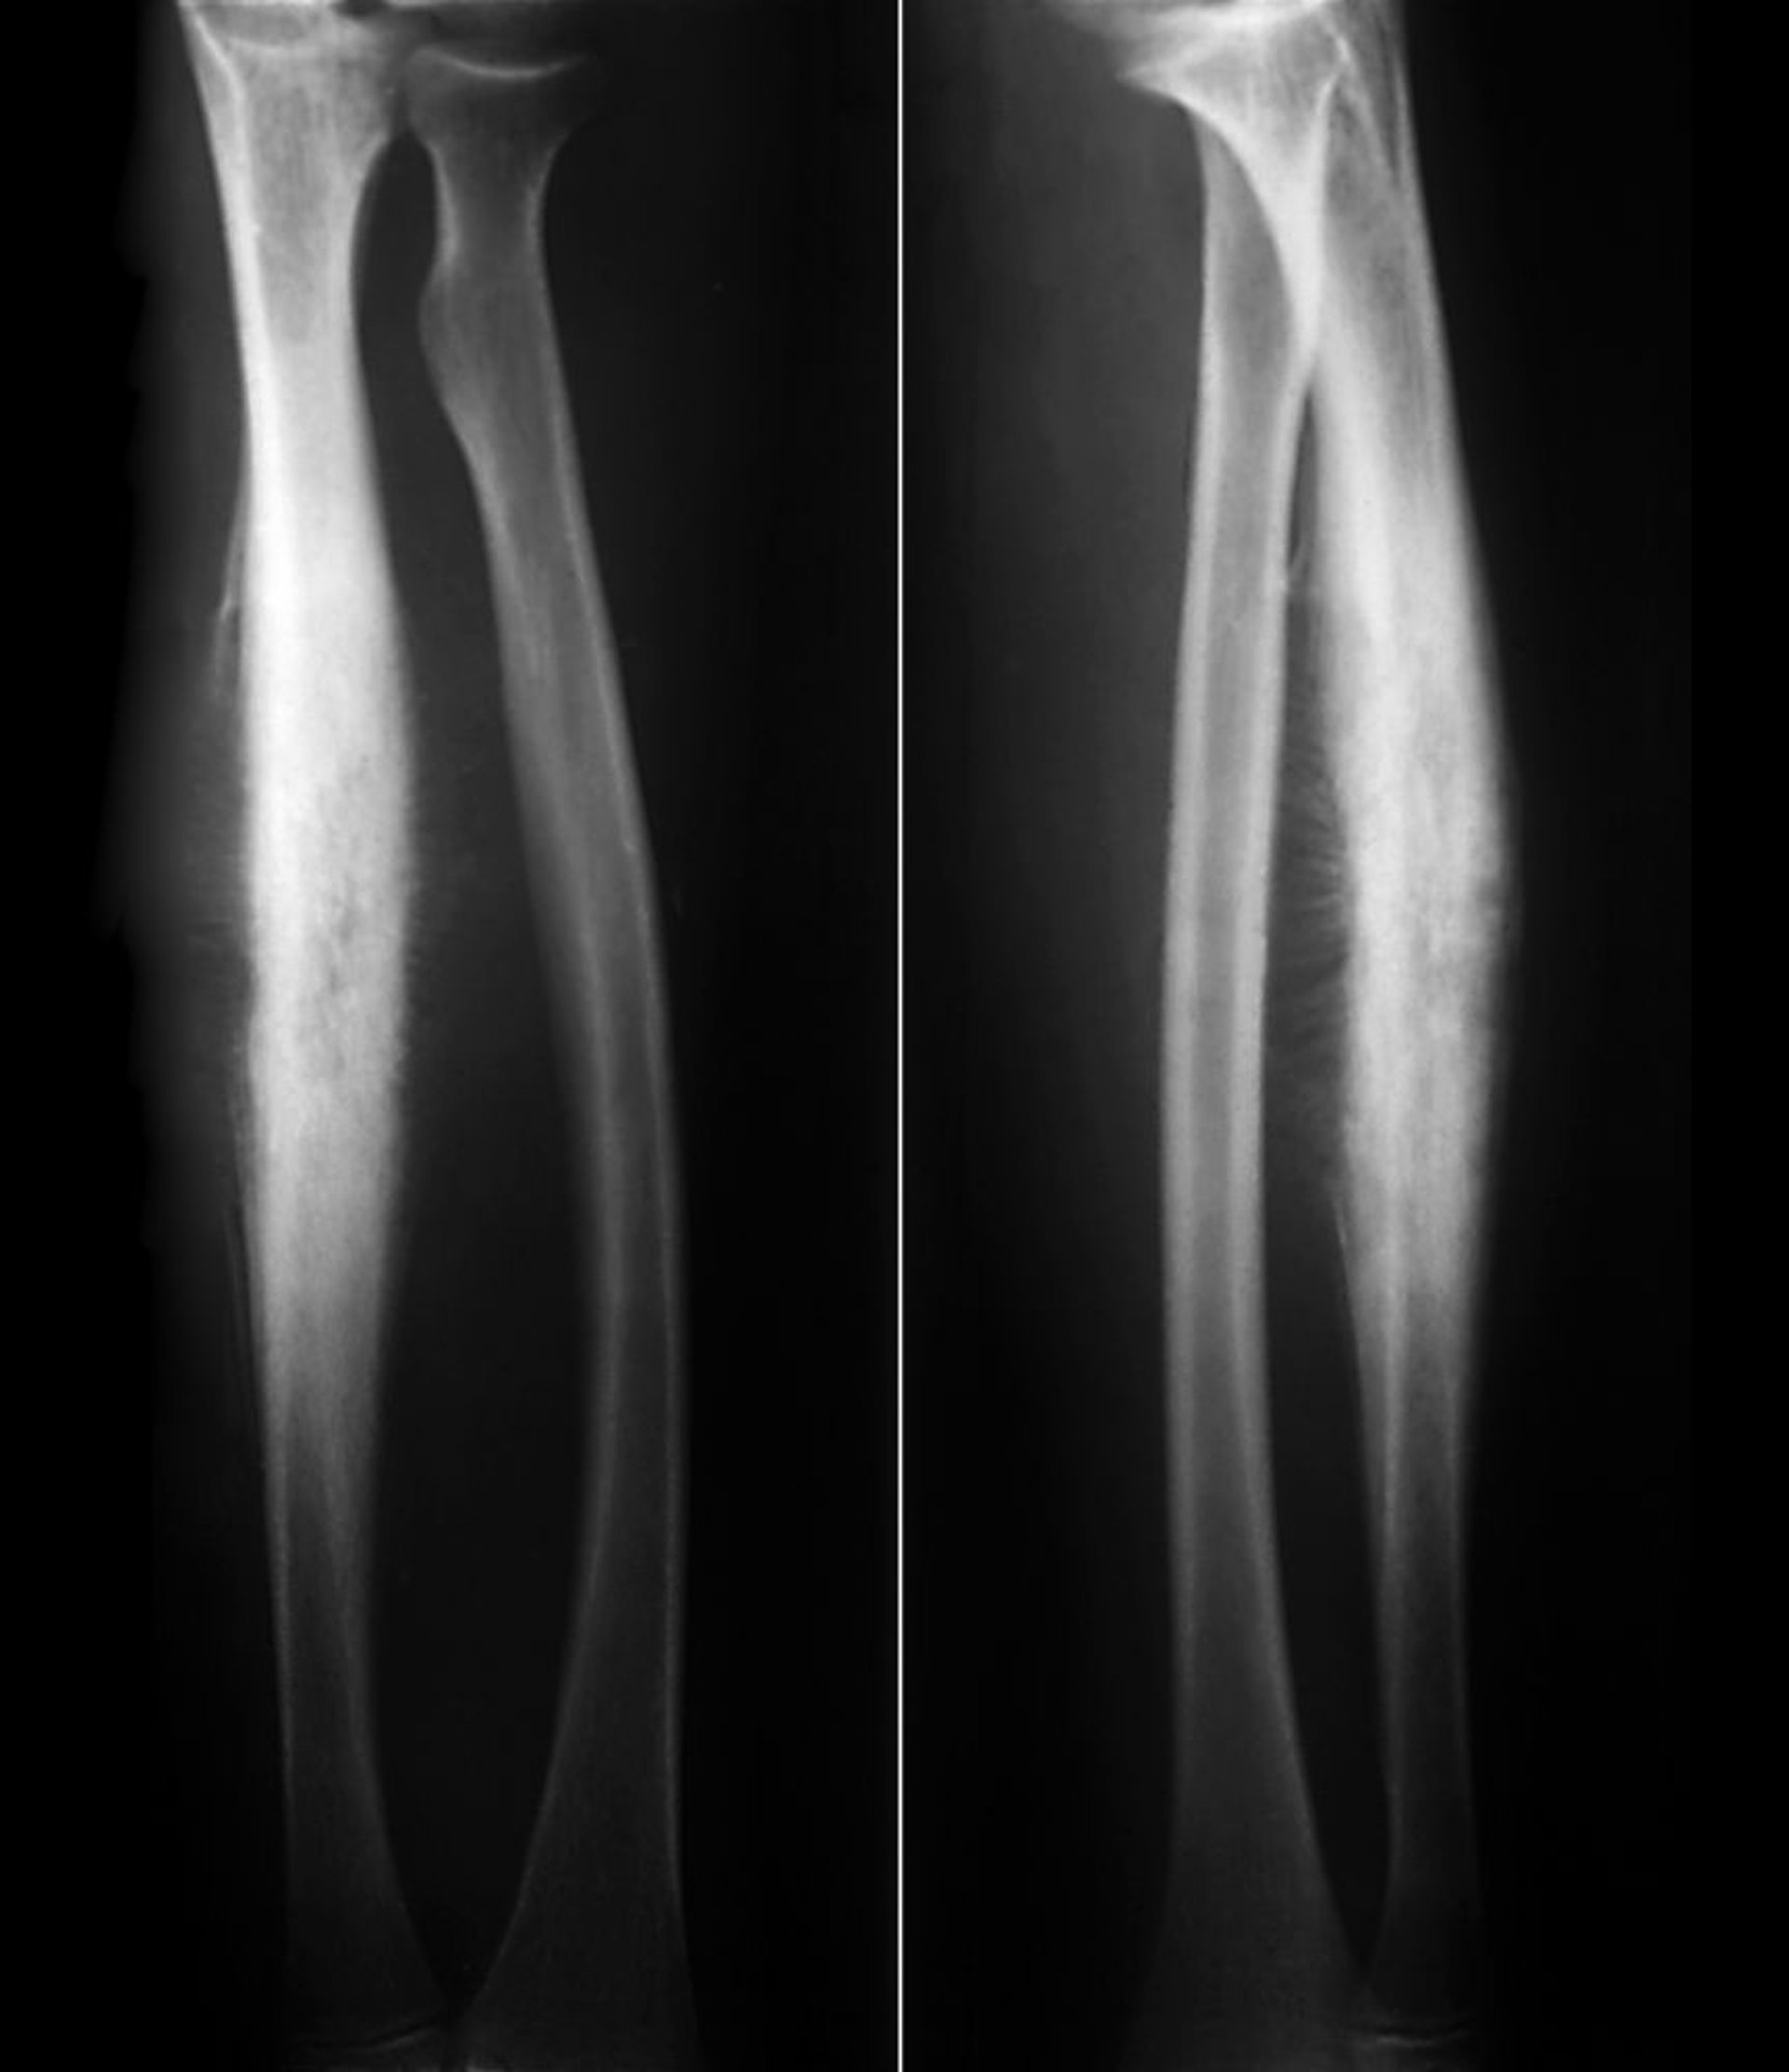

Sarcoma de Ewing do rádio

Esse sarcoma de Ewing da haste radial mostra nova formação óssea reativa subperiosteal em uma reação periosteal clássica com aparência de "explosão solar" junto com destruição lítica do osso cortical.